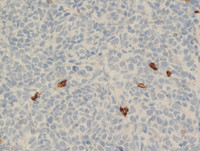

Pranav Pramod Pat...

T-lymphoblastic l...